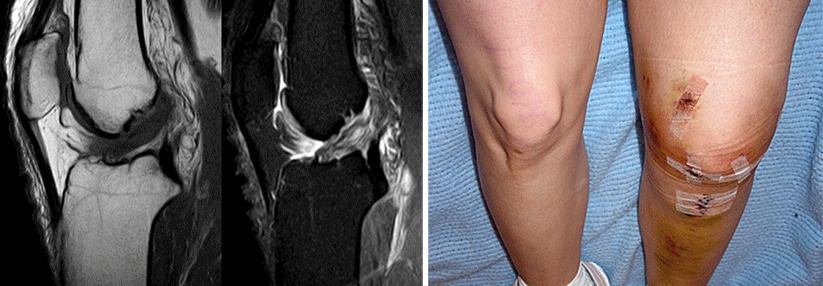

Fast zwei Drittel der Fußballer stehen gut ein Jahr nach Kreuzbandrekonstruktion wieder auf dem Feld. Sechs Jahre später sieht es ganz anders aus.